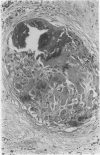

AIMS: To assess the incidence of foreign body giant cell reactions and ossification in benign/melanocytic naevi; and to examine their pathological features to gain an insight into their pathogenesis. METHODS: Intradermal (n = 185) and compound naevi (n = 110) from a routine histology service, together with 60 naevi submitted to an ophthalmic pathologist, were examined for foreign body reactions and ossification. Additional cases were identified prospectively in the course of routine reporting. The clinical and pathological features of positive cases were assessed. RESULTS: Foreign body reactions were identified in nine (4.9%) intradermal and four (3.6%) compound naevi, but in none of the naevi from around the eye. One intradermal naevus showed ossification. A further 11 naevi showing foreign body reaction and five showing ossification alone were identified prospectively. The 24 naevi showing a foreign body reaction had a similar age and sex distribution to controls but were more likely to occur on the head and neck. The reaction usually occurred deep to the naevus, sometimes in relation to a hair follicle, and fragments of hair or keratin were identified in most. Osteoid or bone was present within the reaction in five. In six other naevi, all from the head and neck of women, osteoid or mature bone was present deep to the naevus in the absence of a giant cell reaction. CONCLUSIONS: Foreign body giant cell reactions occur not uncommonly in relation to benign naevi, as a result of follicular damage, possibly due to trauma. The similar siting of foci of bone suggests that ossification occurs as a secondary phenomenon in these cases.